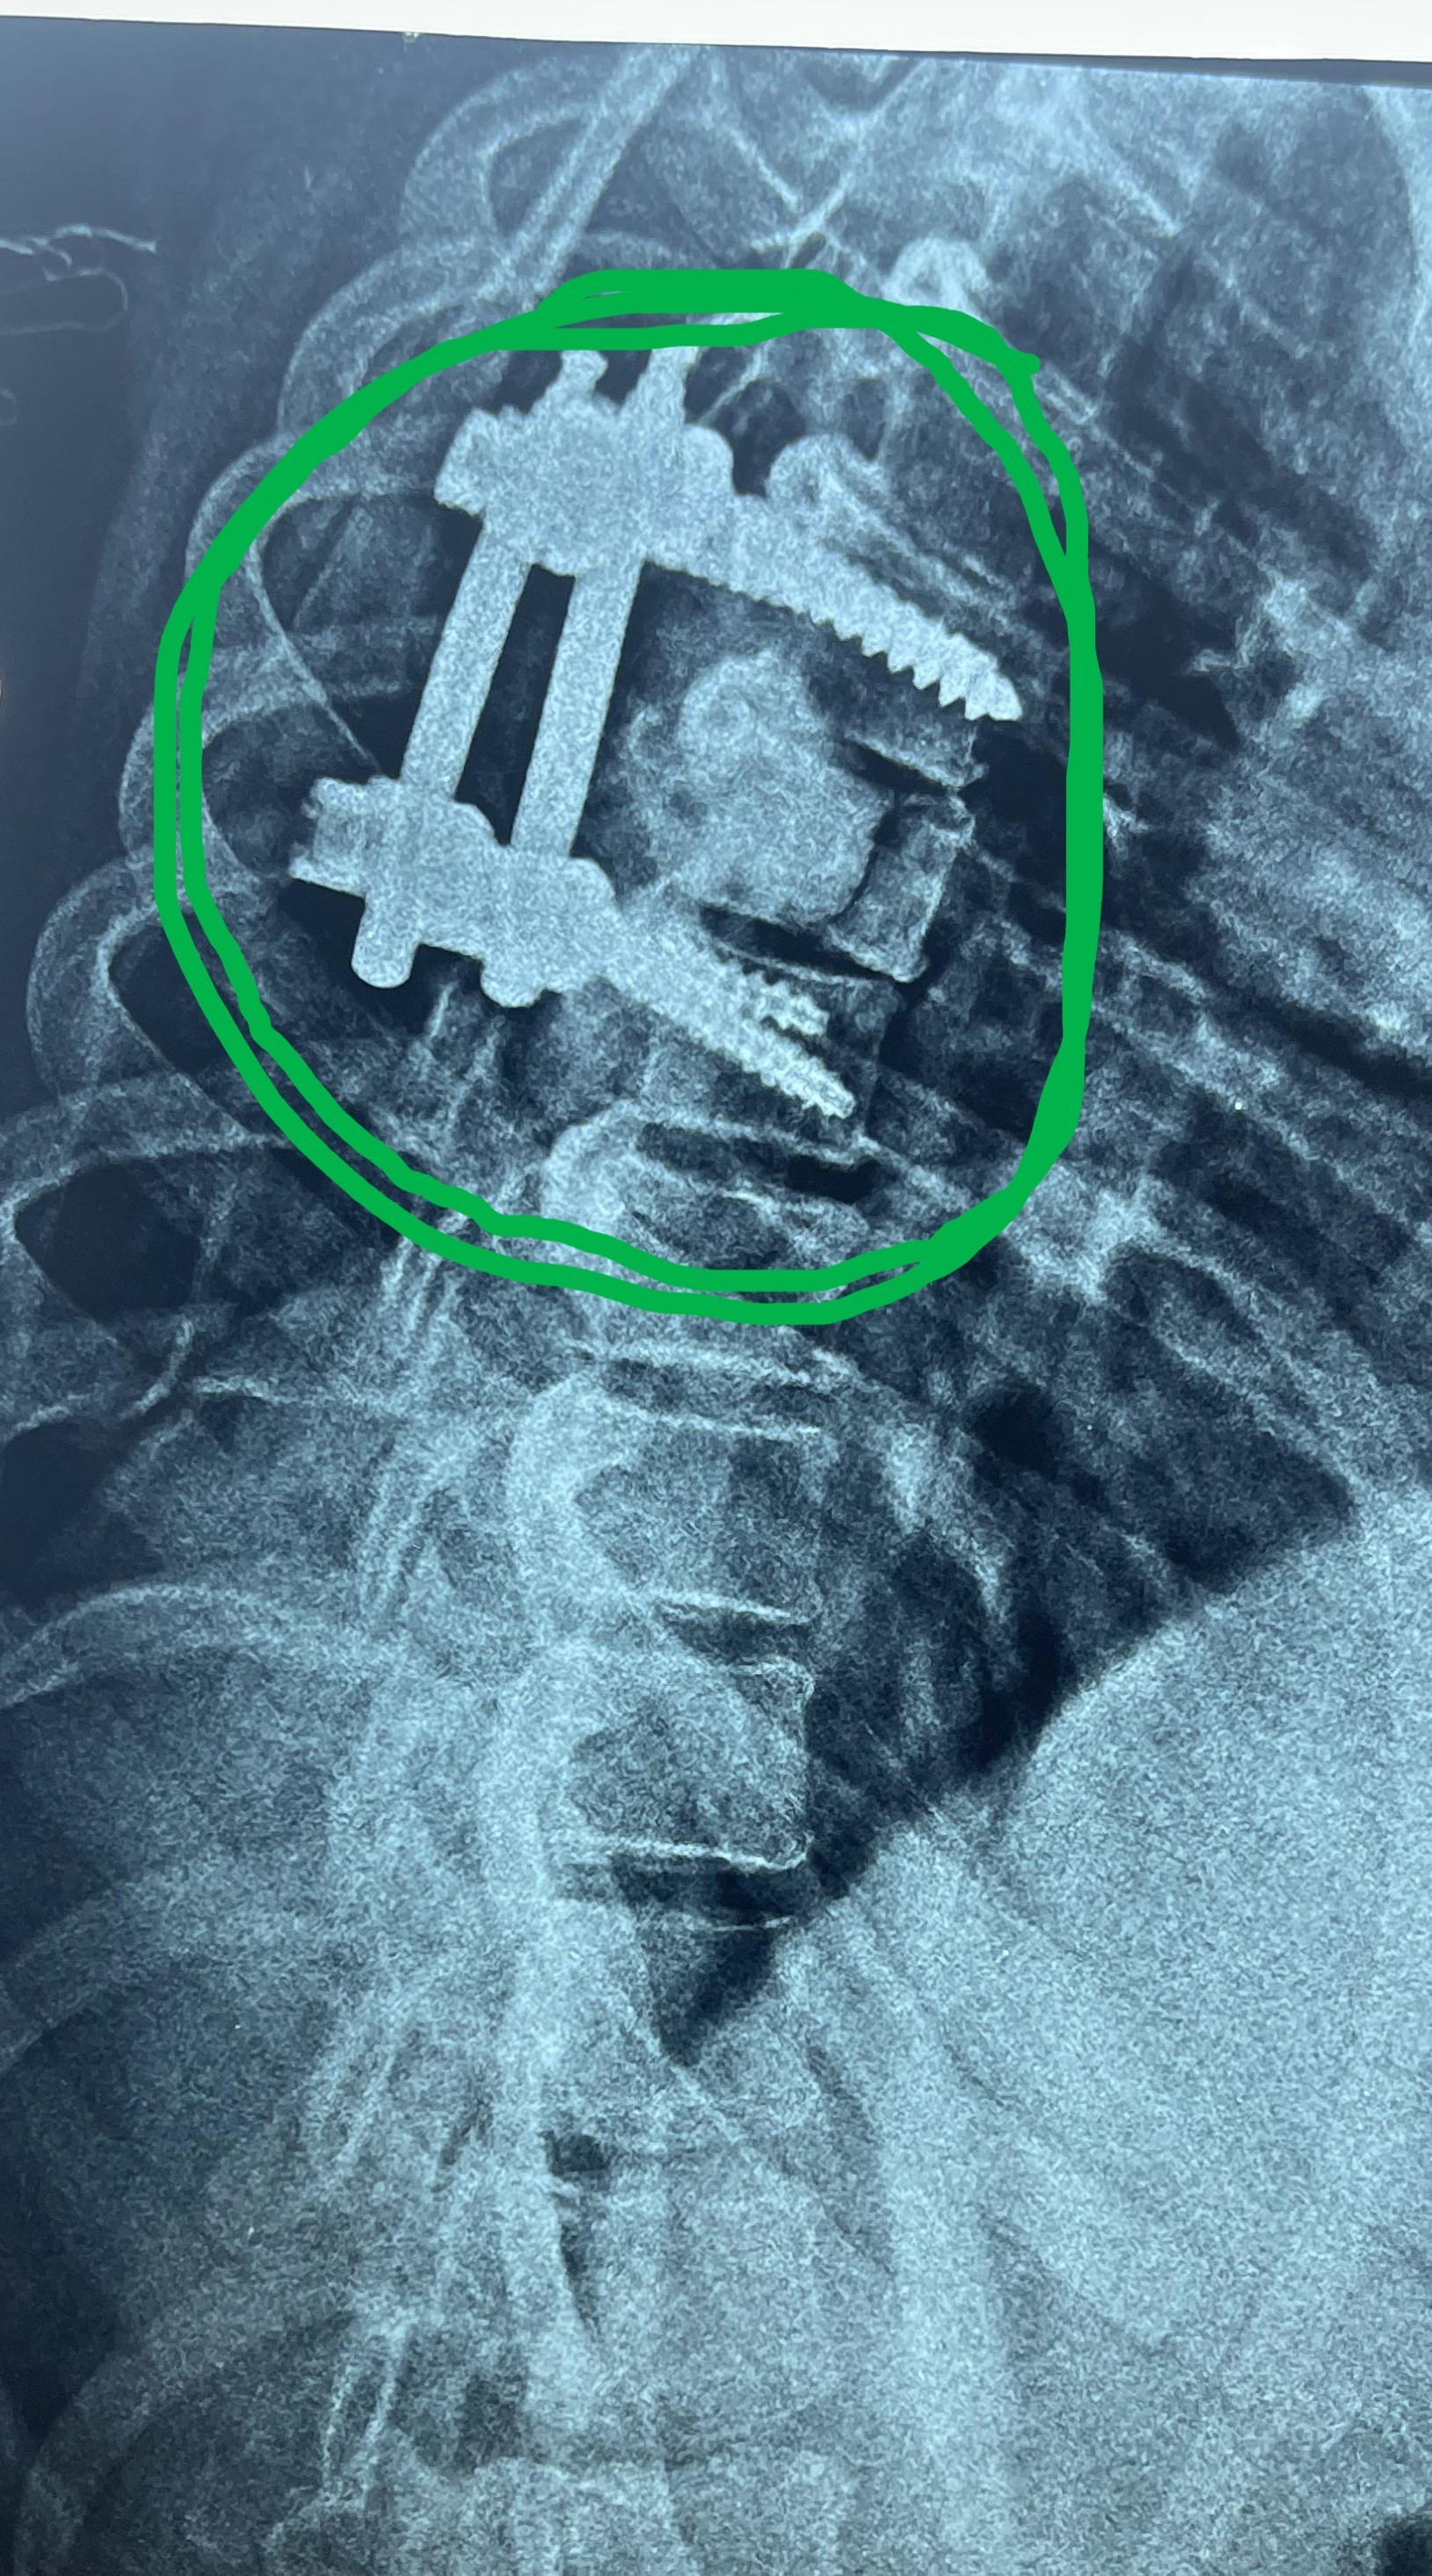

A 43-year-old woman suffering from progressive weakness in both lower limbs was diagnosed and treated. This condition affects walking ability and mobility, requiring thorough neurological evaluation to determine the underlying cause and develop an appropriate treatment plan.

Goal of Treatment:

• Identifying exact cause of neurological weakness

• Developing comprehensive treatment plan

• Restoring muscle strength and motor function

• Improving quality of life and mobility